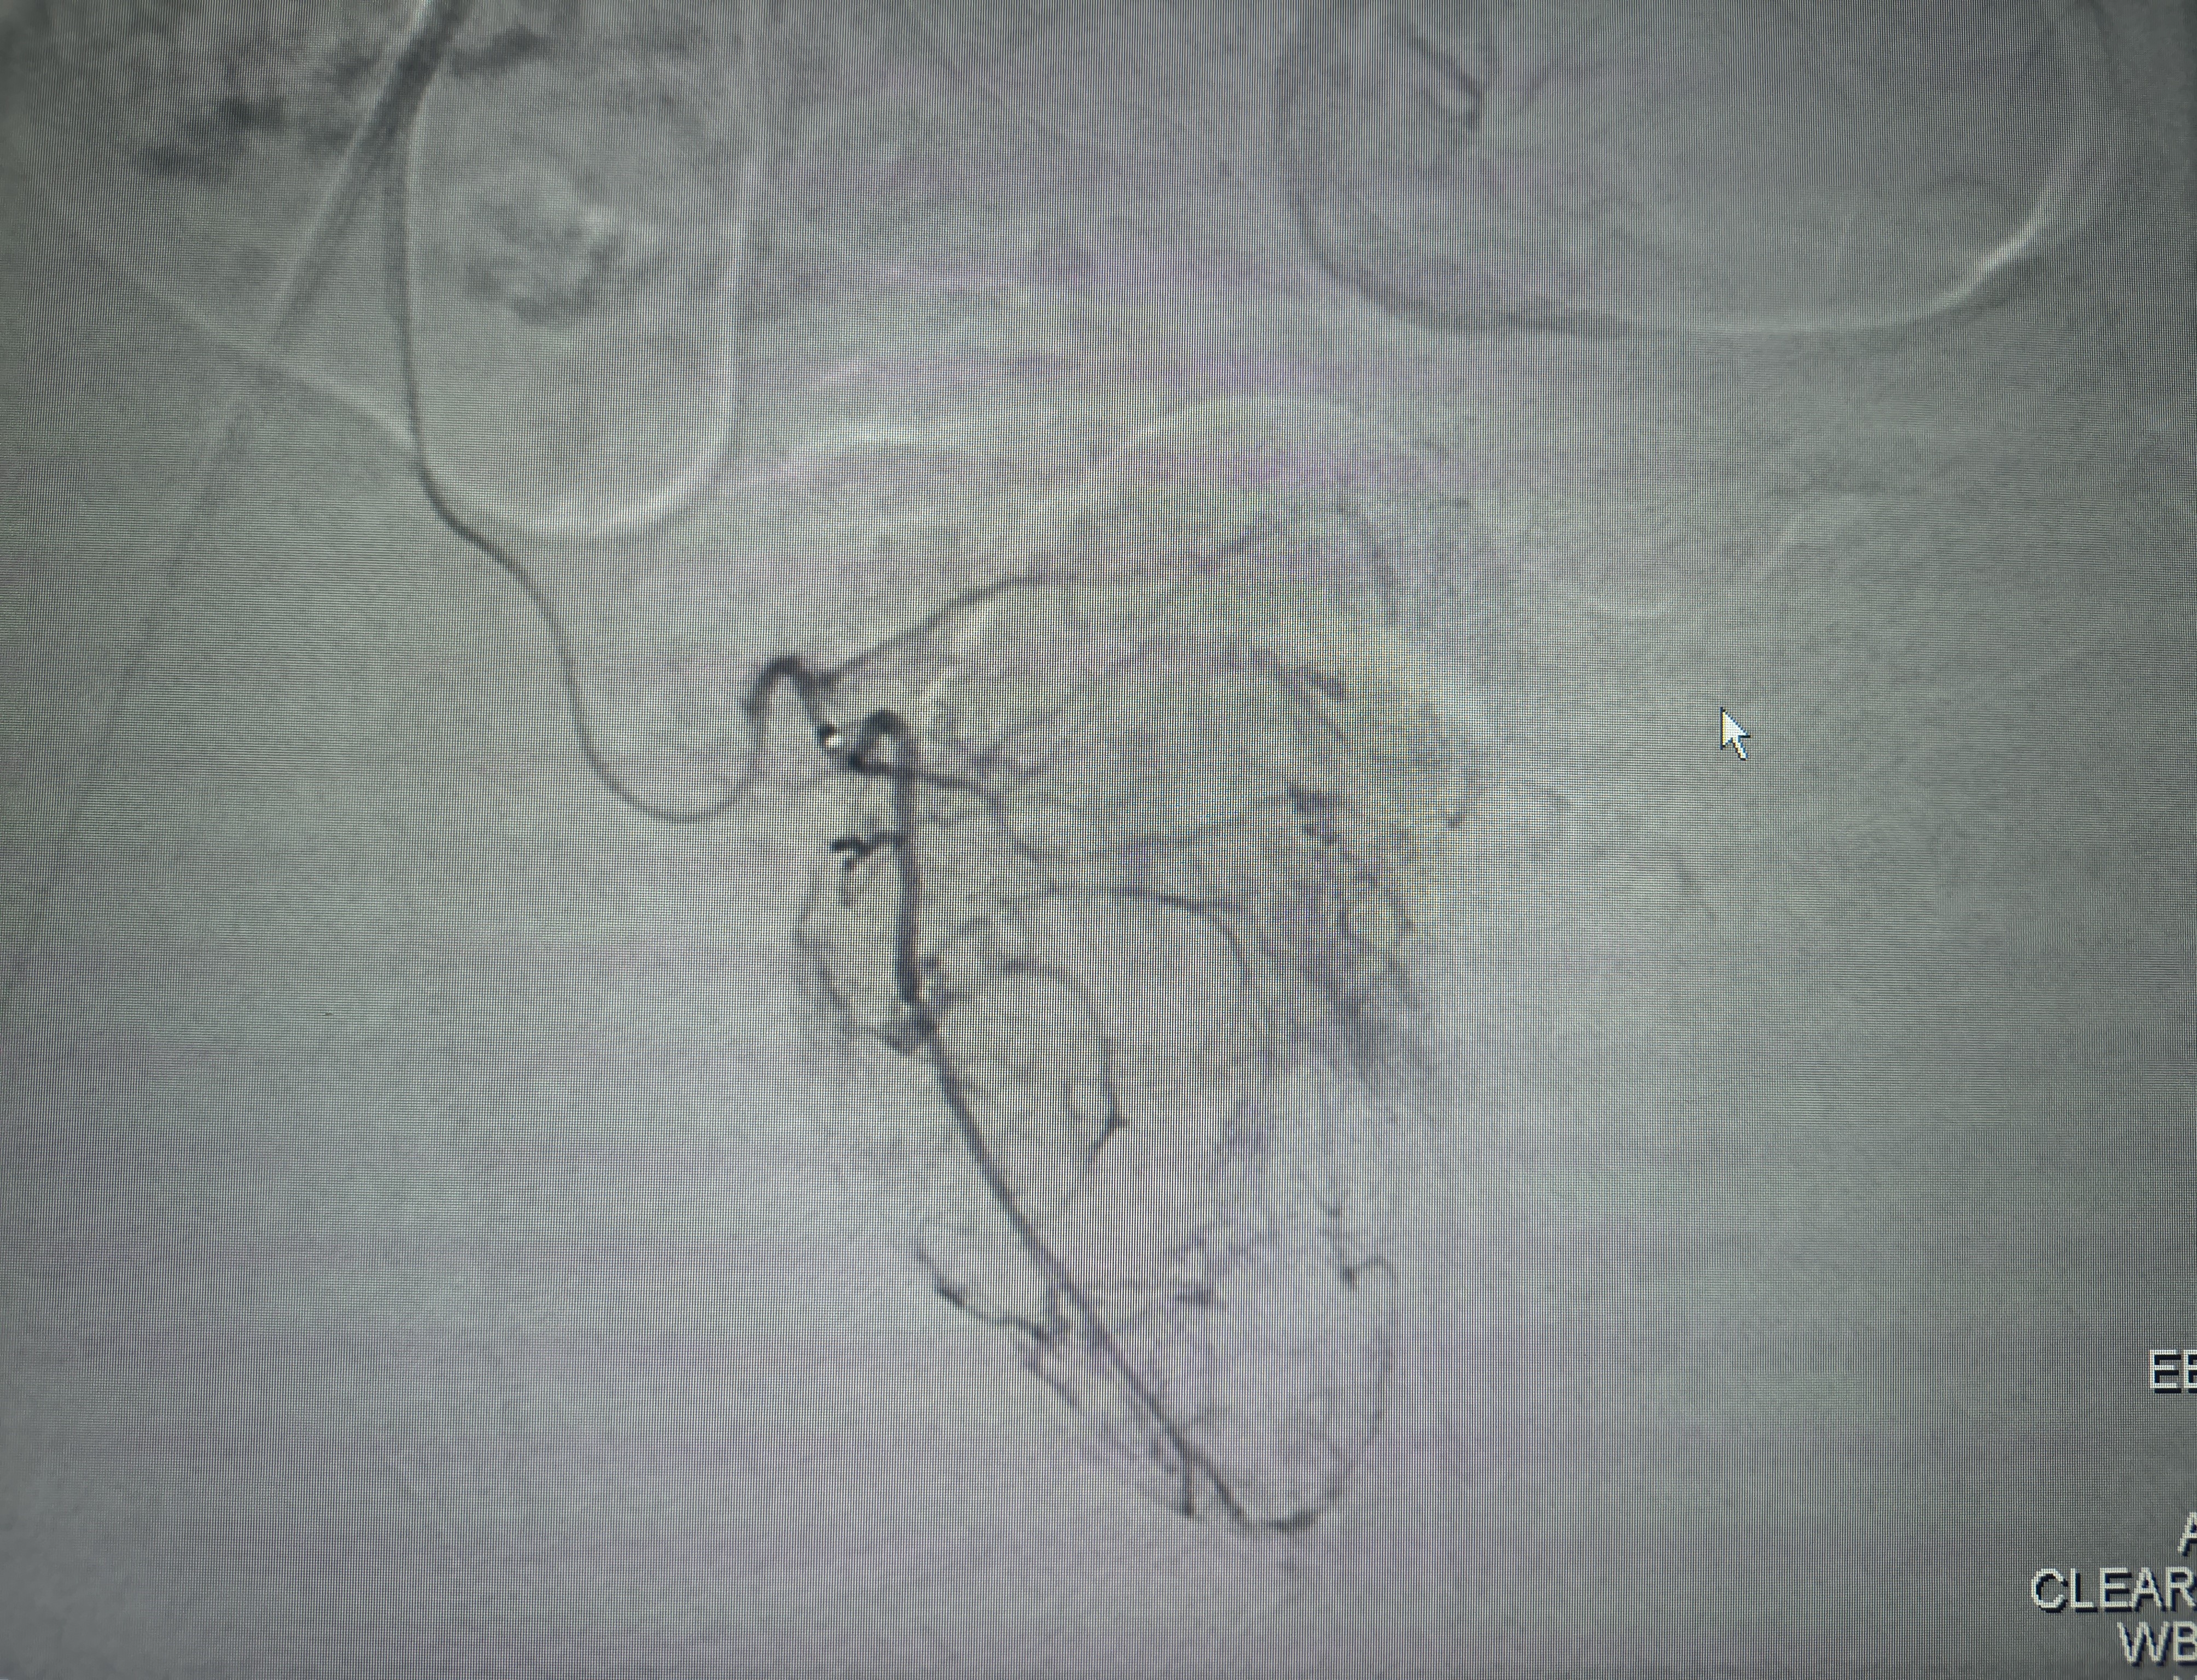

AVM embolisation